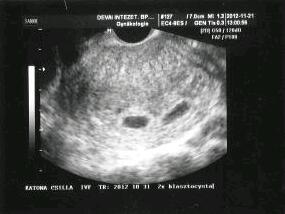

Kettő 2mm-es poronty van és még egy sejlik.

D. azzal kezdte, a HCG-m láttán, h lehet, h méhenkívüli. Majd bedugta a fejet és csak keresgélt, keresgélt és egyre csak vártam a felfedezés örömét az arcán, de csak nem jött. Majd kiküldött pisilni!!! Aztán végre látta őket, na itt vannak ezek. Huuuuuuu.

Se élők se holtak nem vagyunk, laírhatatlan érzés, kívánom tapasztaljátok meg mindannyian!!!

Jelentem 3in1 Tigrismama lettem:-) Megvan mind a kettő bébi, D azt mondta egyik szebb,mint a másik!!!:-) A vizsgálat után D nyakába ugrottam és adtam 2 puszit, ő meg kifelé menet még megdobott kettővel örömében:-)

Itt vannak a Tigrisbigrisek:

Kép

Jelentem nagycsalàdkènt tàvoztunk Apànktól! 3 picikét visszakaptuk,egy egèsz óràt feküdtem bent! Sajnos van megint víz a hasamban,megyünk haza ès nyomom a húsokat! Köszi a sokk drukkot lànyok!

sheil, Babyboom: újbóli gratula megint.Örûlök,hogy talàlkoztunk ès pihenjetek sokat! Babyboom örülök,hogy megismételték! 4 sejtésem voltak a picik,azt mondtàk,hogy nagyon szèpek!